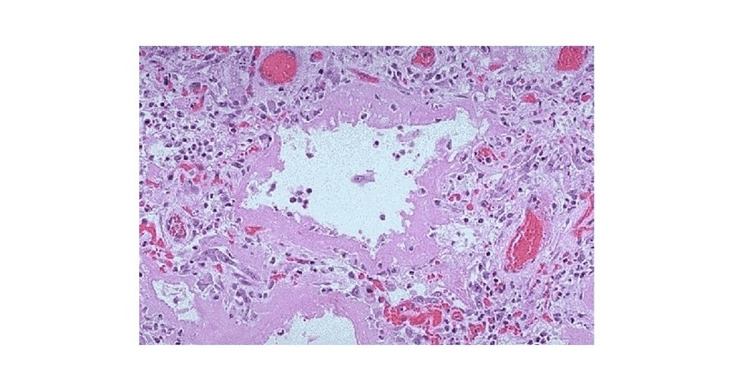

Given the non-specific nature of the CT findings and in the context of the previous workup, the patient was sent for an open lung biopsy. A right lung wedge biopsy was performed, and the tissue was sampled from the patient’s upper, middle, and lower lobes. These tissue samples were reviewed by both a pathologist at the home institution and a specialist in pulmonary pathology. These samples showed alveolar damage with eosinophilia, a representation of which can be seen in Figure 2.

Diffuse alveolar damage secondary to inflammation of the parenchymal epithelium is the most commonly seen pathology associated with EVALI [ref. 17]. The toxic insult results in edematous changes, epithelial cell death, and sloughing of multiple cell layers, and if the toxic inhalant quantity is significant and sustained over an extended period, this inflammation can lead to the formation of hyaline membranes and fibroblast proliferative changes [ref. 17].

Interesting features of this case include the histological finding of diffuse alveolar damage accompanied by eosinophilia, which can be suggestive of eosinophilic pneumonia. Many cases of acute-onset eosinophilic pneumonia have been observed following exposure to vaping or e-cigarette usage. However, in each of these cases, the duration of time between e-cigarette use and symptom onset was a few weeks. In this case, the patient had almost a decade of exposure before he became symptomatic [ref. 4,ref. 19]. Another interesting feature is the patient’s delayed development of eosinophilia as prior bronchoscopy with bronchoalveolar lavage did not reveal this finding.